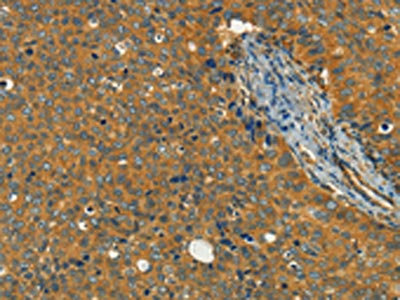

The image on the left is immunohistochemistry of paraffin-embedded Human brain tissue using CSB-PA907505(KLC1 Antibody) at dilution 1/40, on the right is treated with fusion protein. (Original magnification: ×200)